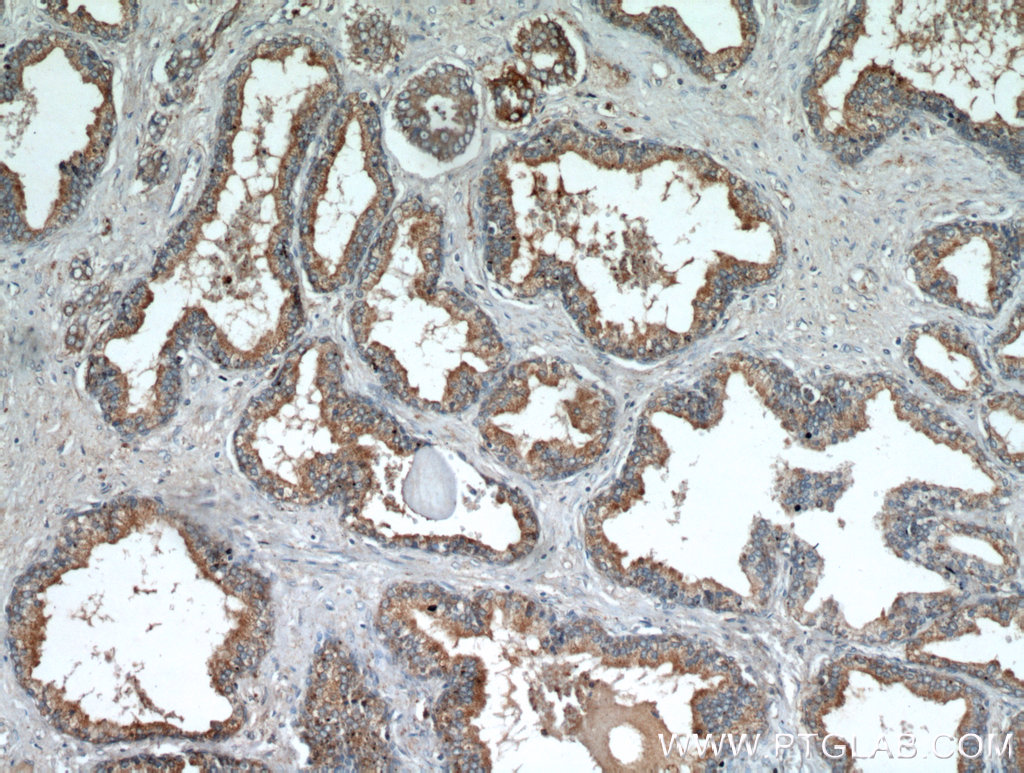

| Positive IHC detected in | human prostate hyperplasia tissue, human heart tissue | ||

| Recommended dilution | WB : 1:500-1:5000 IP : 1:200-1:2000 IHC : 1:50-1:200 IF : 1:10-1:100 |